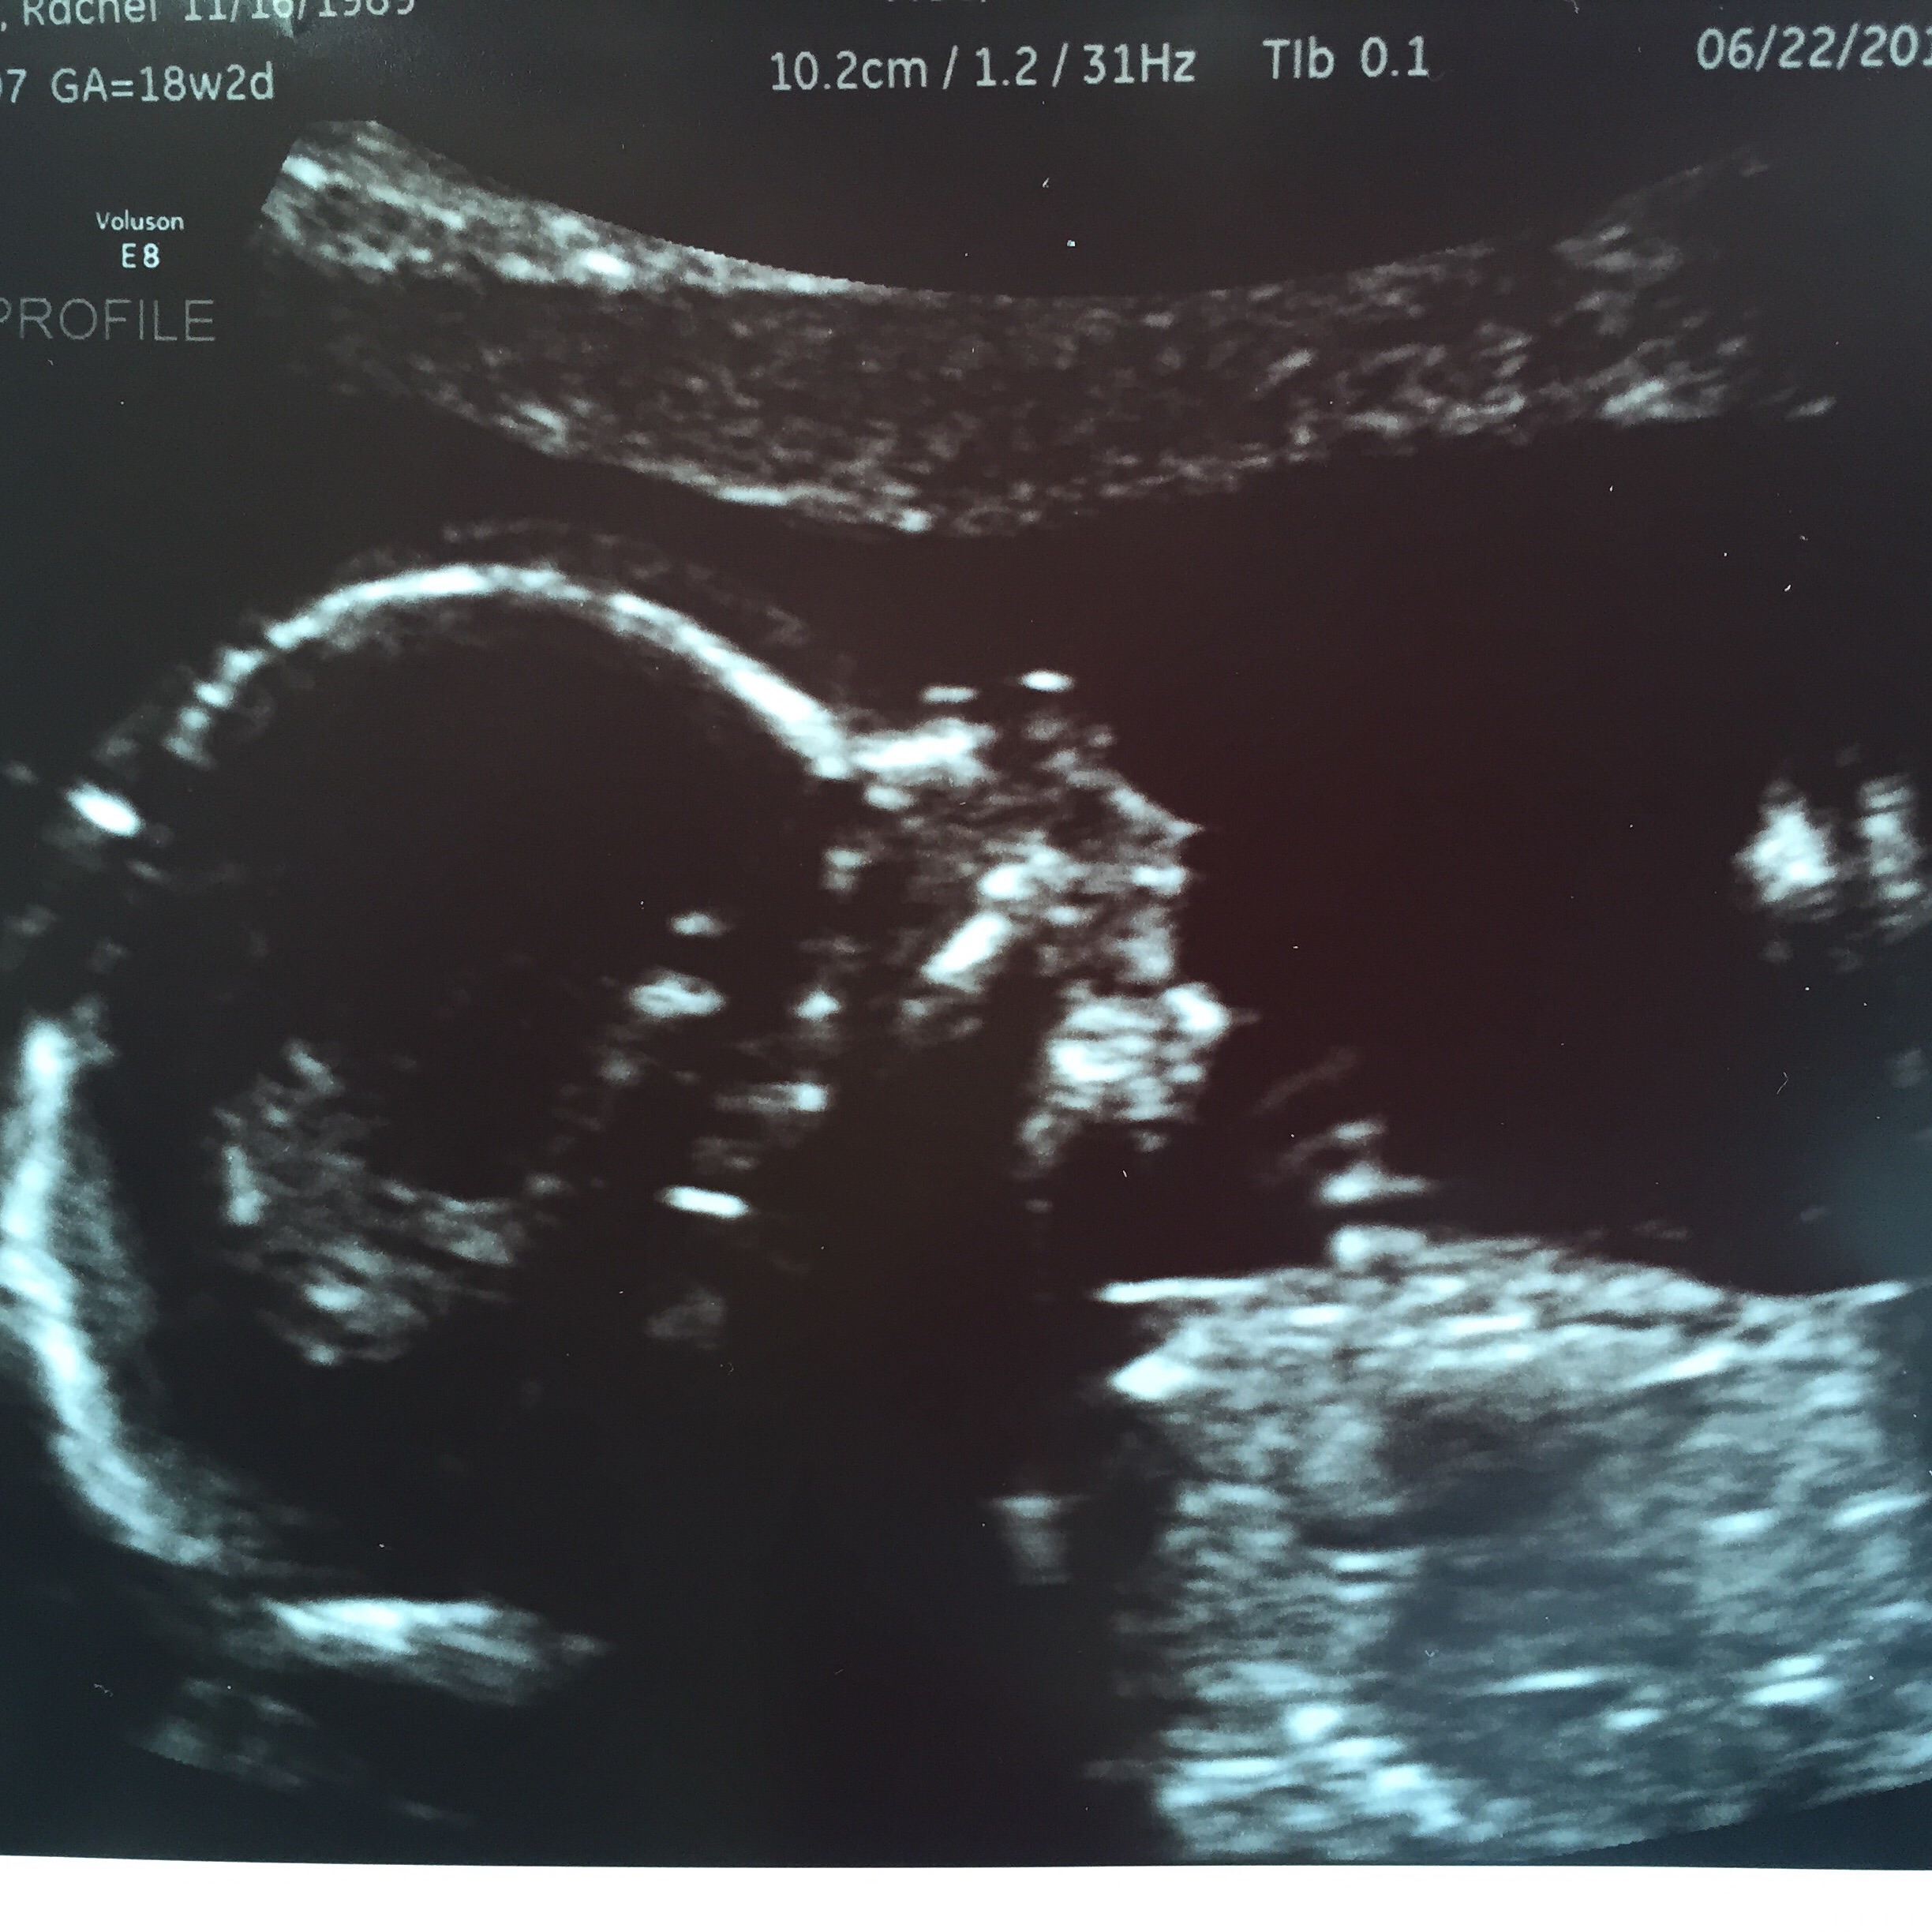

19 weeks today and Just curious on what everyone thinks the little nugget might be!?!? We find out Friday at our reveal party but that's so far away!!!

There is a theory that you can guess sex by head shape... BUT considering you're only 19 weeks it probably wouldn't be too accurate considering the head is still forming.

My guess is.... It's a baby. CONGRATULATIONS!!! =D> We can't tell you what your having, we are not professional Ultra Sound Techs, and you've posted only the head.

Ps this is only the top half of your baby anyway

We can't tell you what your having, we are not professional Ultra Sound Techs, and you've posted only the head.